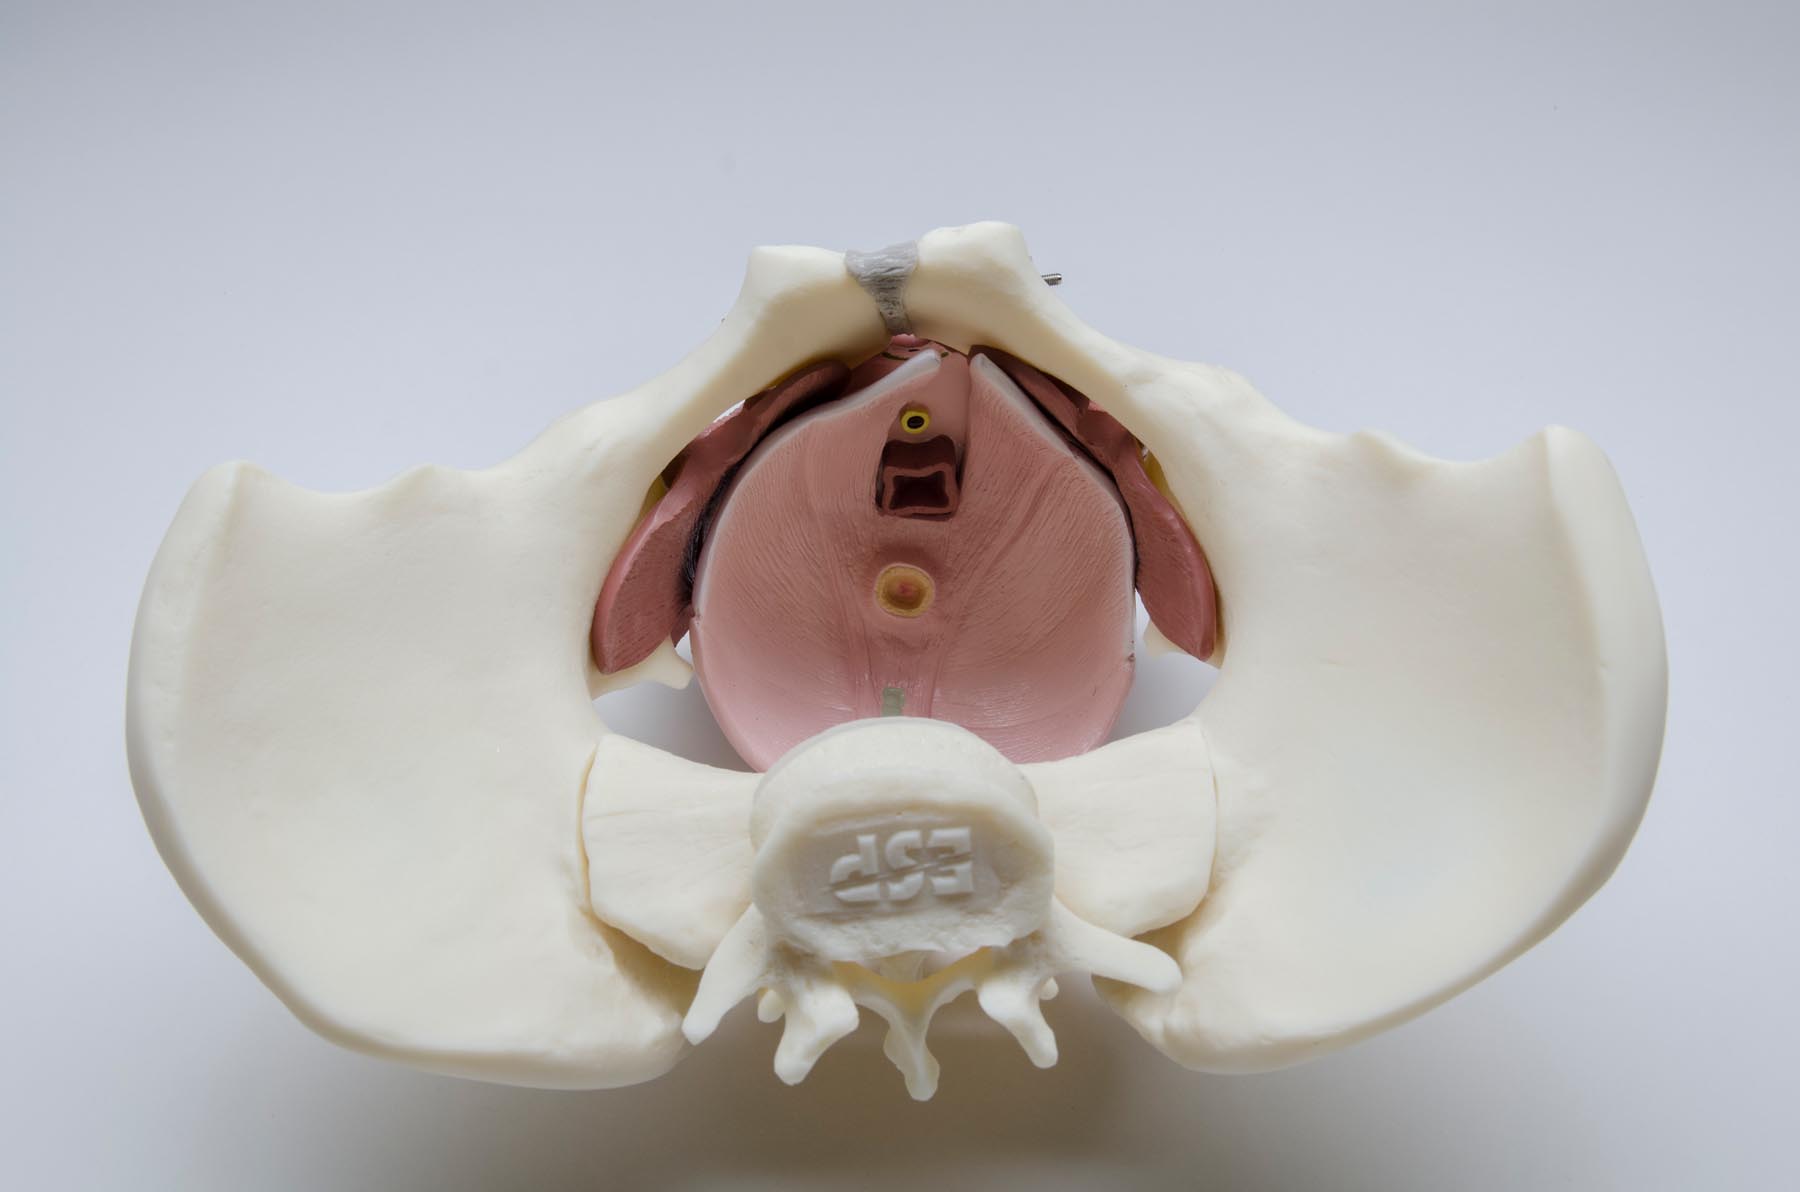

A complete life-size female pelvis with a highly detailed pelvic floor made of flexible plastic. Features the genitalia and associated muscles. Dissects into 5 parts.